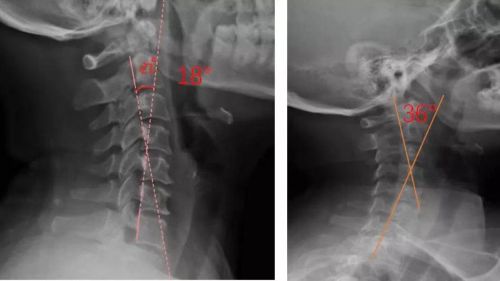

患者適配前后側(cè)位X光,佩戴前18°,適配后36°

對(duì)于頸椎病患者,合理設(shè)計(jì)的頸椎枕,能夠緊密適合頸椎,矯正頸椎生理曲度;再根據(jù)頸椎曲度改善情況,隨時(shí)間慢慢調(diào)整3D打印頸椎枕曲度,使變直的頸椎逐漸形成正常的生理曲度,改善頸肩痛的癥狀。